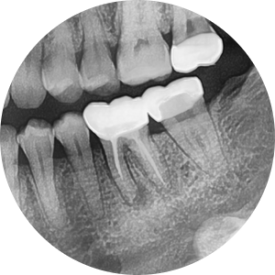

파노라마 엑스레이를 먼저 볼까요?

(정확한 진단에는 전체를 보는 눈이 필수입니다!)

왼쪽 아래 어금니 뿌리 주변이 심상치 않네요...

확대해보겠습니다.

파노라마를 확대해보니,

뿌리 쪽으로 까맣게 뼈가 녹아내린 모양이 관찰됩니다.

보다 정확한 진단 및 상황파악을 위해

치근단엑스레이를 추가로 촬영하였습니다.